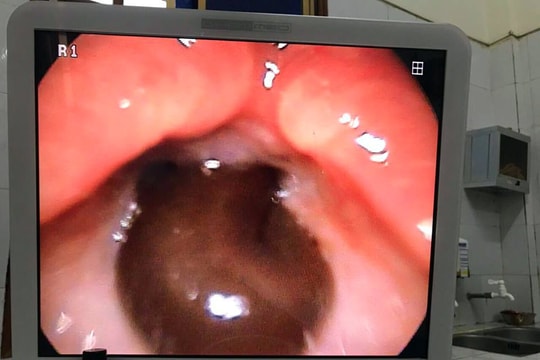

Horrifying moment a leech crawled into the airway of a 9-year-old child in Nghe An

October 26, 2018 11:01

(Baonghean.vn) - On October 26, the Department of Otorhinolaryngology - Nghe An Obstetrics and Pediatrics Hospital informed that doctors had just removed a 5cm long leech from the airway of patient Luong Thi Toi (9 years old), resident...